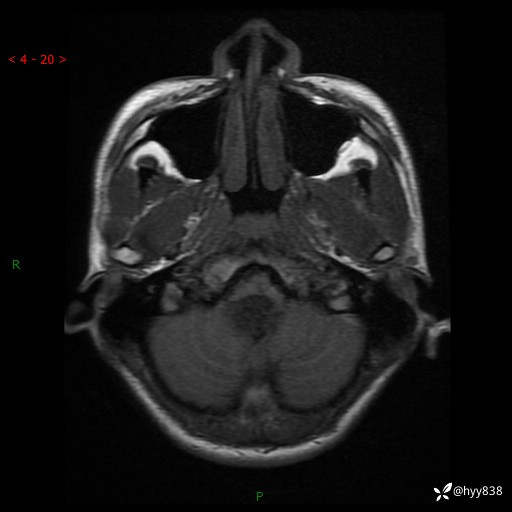

性别:男

年龄:17岁

简要病史:头痛伴间断性呕吐1月余,外院CT提示颅脑占位

颅脑MRI平扫+增强